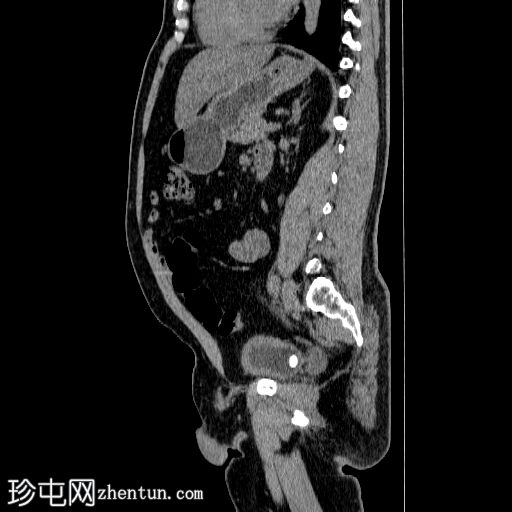

矢状位

平扫

在左侧输尿管膀胱连接处可见一枚24×15 mm的大膀胱结石。膀胱壁轻度弥漫性增厚,厚度约6 mm,提示膀胱炎。

左肾上极发现一单纯性皮质囊肿,Bosniak I 型,大小为 13 mm。

可见多个副脾(脾小体),位于主脾实质的上方和下方,在影像学各期均表现出与脾脏相似的衰减值。

肝脏弥漫性脂肪浸润。